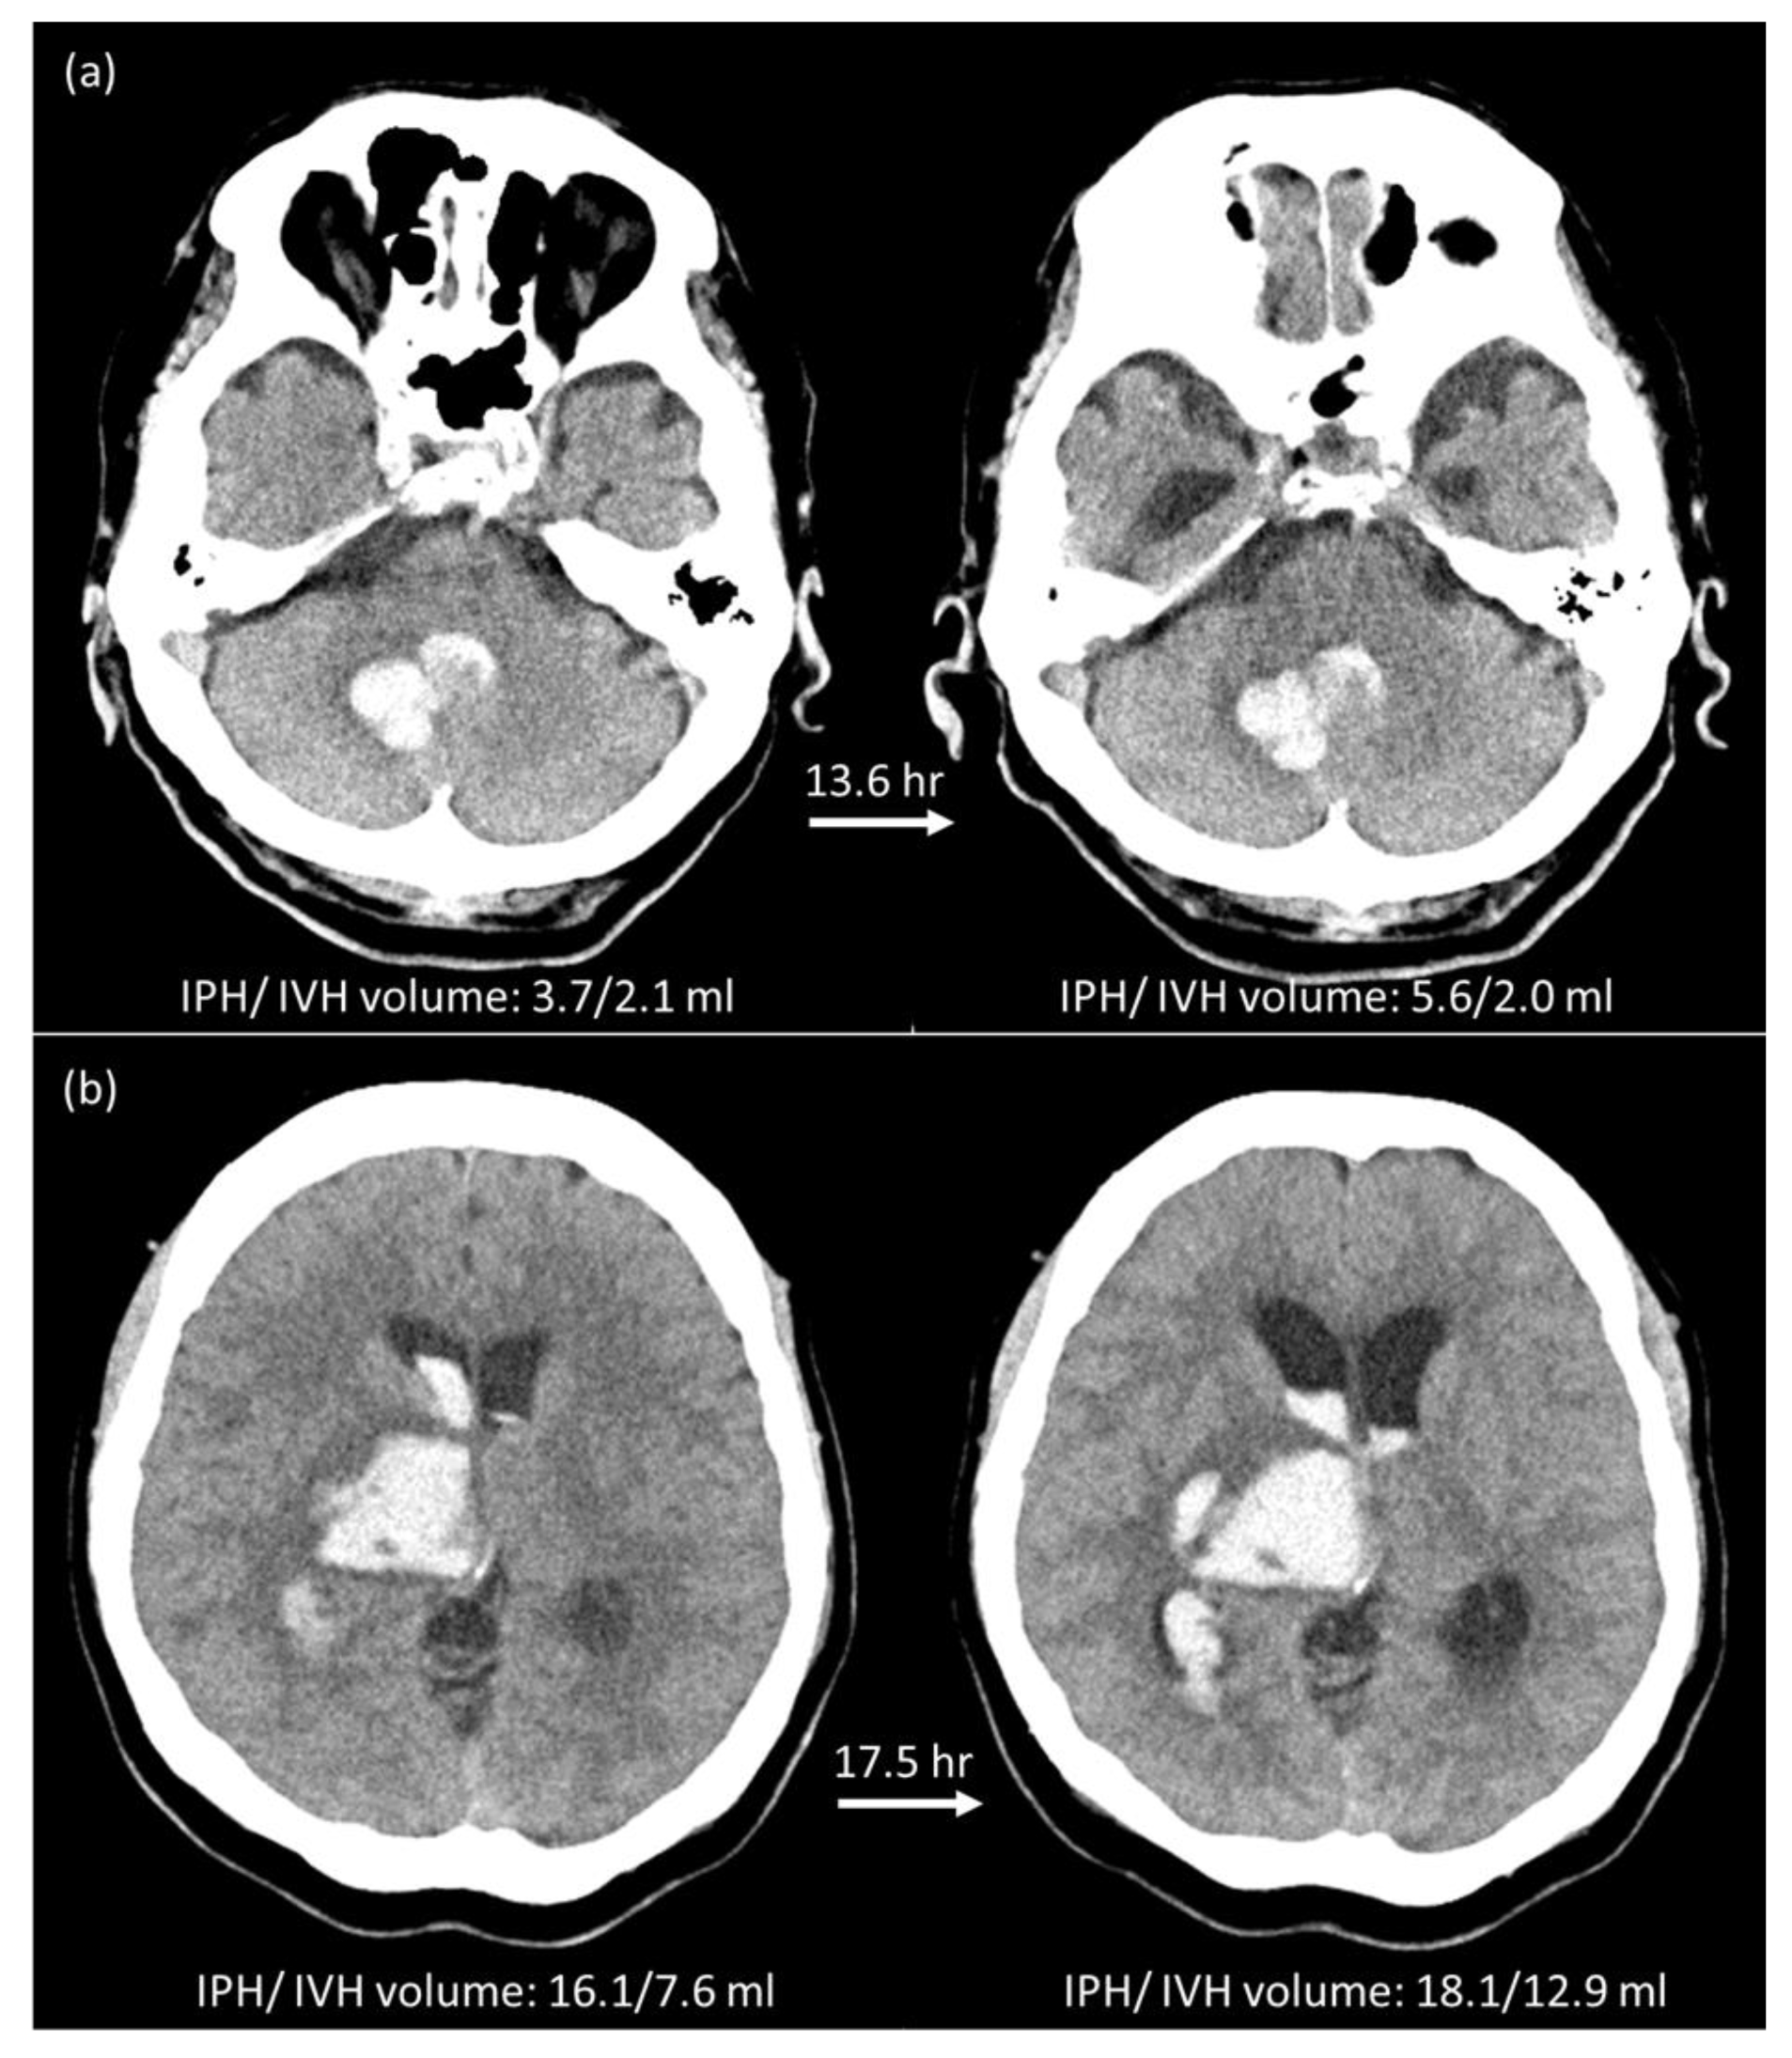

2.5. Manual Hematoma Segmentation and HE Definition

3.1. Hematoma Expansion Status Defined by IPH (HEP)

3.2. Hematoma Expansion Status Defined by IPH + IVH (HEP+V)